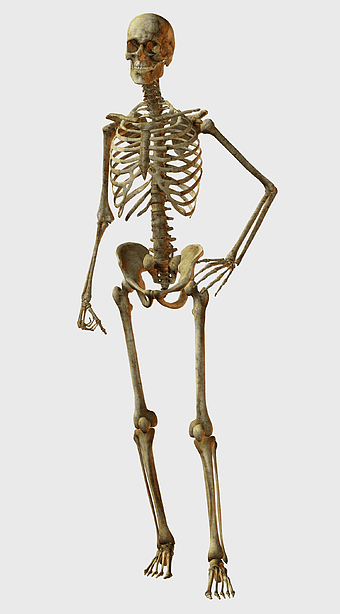

spine skeleton illustration, orthopedic surgery, musculoskeletal disorder, human body anatomy, skeletal health, medical imaging, spine health analysis -

Human skeleton, rib cage anatomy, upper limb bones, joints in human body, skeletal structure analysis, vertebral column details, anatomical illustration study -

physical therapy for body recovery, skeletal structure medical illustration, mckenzie method technique, manual therapy practices, anatomical joint analysis, musculoskeletal health focus, human body rehabilitation process -